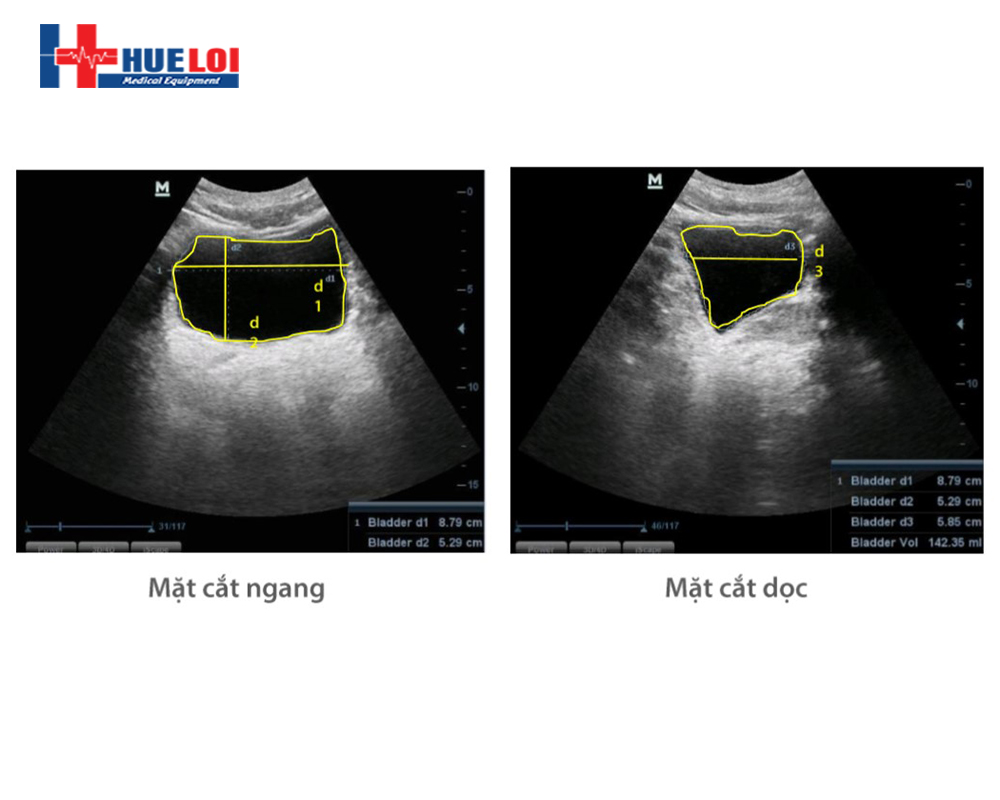

- Tự động dò tìm bờ thành của bàng quang, phát hiện 3 đường kính của bàng quang và tính thể tích bàng quang

- Mẹo sử dụng dễ dàng hơn:

- Trình tự quét: Mặt cắt ngang sau đó mặt cắt dọc

- Để bàng quang ở trung tâm của hình ảnh

- Thể hiện rõ viền, bờ thành của bàng quang